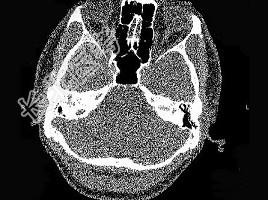

- 单项选择题男,23岁,右耳流脓十余年,右外耳道流脓,鼓膜穿孔,CT检查如图,最可能诊断为 ( )